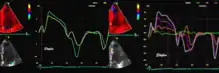

Colour tissue Doppler

Unlike spectral Doppler, colour tissue Doppler samples velocities from all points of the sector, by shooting two pulses successively, and calculating the velocity from the phase shift between them by autocorrelation. The calculation is slightly different from the true Doppler effect, but the result becomes identical. This results in a single velocity value per sample volume. The result is a velocity field of (nearly) simultaneous velocity vectors towards the probe. The advantage of colour Doppler over spectral Doppler is that all velocities can be sampled simultaneously. The disadvantage is that if there is clutter noise (stationary reverberations), the stationary echoes will be integrated in the velocity calculation, resulting in an under estimate. As pulsed wave Doppler are displayed as a spectrum, the colour Doppler values will correspond to the mean of the spectrum (in the absence of clutter), giving slightly lower values. In the HUNT study, the difference in peak systolic values were about 1.5 cm/s.[26]

The local velocities are not the result of the local function, as segments are moved by the action of neighbouring segments. Thus the velocity differences velocity gradient are the main measure of regional contraction, and has become the most important employment of colour tissue Doppler, in the method of strain rate imaging.[27]